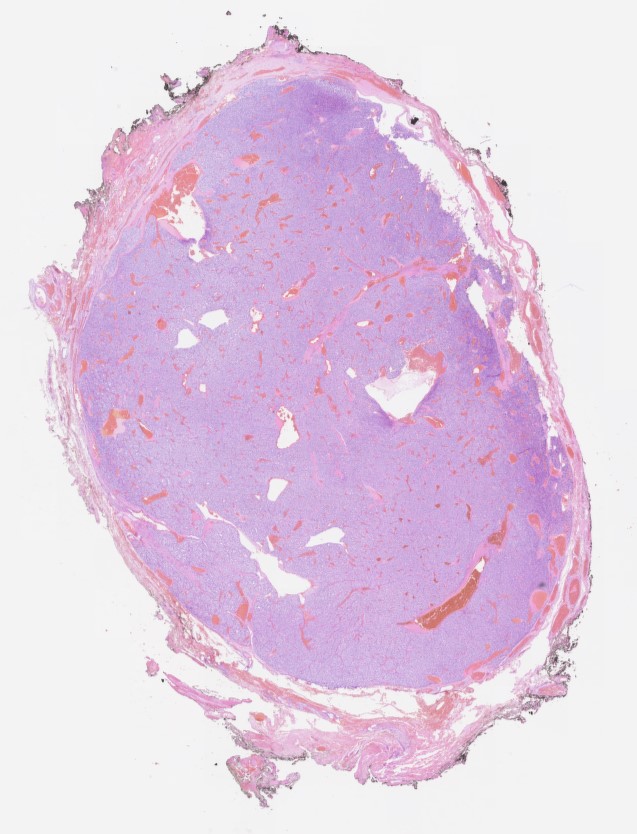

A 76 year old woman presented with a right sided neck mass which was excised. Macroscopically it was a grey solid nodule measuring 20 x 15 x 14mm. The outer surface was smooth and the cut surface was also grey and solid.

Carotid body paragangliomas are slow growing, well circumscribed tumors with a reddish-brown, firm cut surface. Hemorrhage and cystic degeneration may be seen. On microscopy, nests of oncocytic cells ("zellballen"), often with prominent intranuclear cytoplasmic pseudoinclusions, are surrounded by a fibrovascular network including small spindled sustentacular cells. As demonstrated by this case, an organoid growth pattern is most common in head and neck paragangliomas, but trabecular and solid growth, spindled areas, pigmentation, stromal sclerosis and even amyloid deposition have been described (Head Neck Pathol 2015;9:300). The sustentacular cells stain with S100 and the tumor cells with neuroendocrine markers (synaptophysin, chromogranin, CD56). A reticulin stain will highlight the fibrovascular network. Management is surgical resection (Arch Pathol Lab Med 2014;138:182).

A 76 year old woman presented with a right sided neck mass which was excised. Macroscopically it was a grey solid nodule measuring 20 x 15 x 14mm. The outer surface was smooth and the cut surface was also grey and solid.

Carotid body paragangliomas are slow growing, well circumscribed tumors with a reddish-brown, firm cut surface. Hemorrhage and cystic degeneration may be seen. On microscopy, nests of oncocytic cells ("zellballen"), often with prominent intranuclear cytoplasmic pseudoinclusions, are surrounded by a fibrovascular network including small spindled sustentacular cells. As demonstrated by this case, an organoid growth pattern is most common in head and neck paragangliomas, but trabecular and solid growth, spindled areas, pigmentation, stromal sclerosis and even amyloid deposition have been described (Head Neck Pathol 2015;9:300). The sustentacular cells stain with S100 and the tumor cells with neuroendocrine markers (synaptophysin, chromogranin, CD56). A reticulin stain will highlight the fibrovascular network. Management is surgical resection (Arch Pathol Lab Med 2014;138:182).